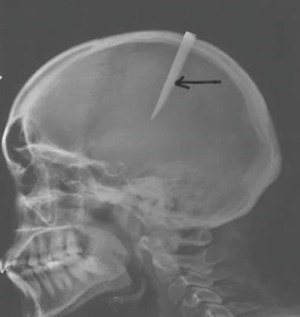

High dose vitamin D3 made a big difference in my trauma patients' quality of life, especially those with severe traumatic brain injuries. A concussion is a mild traumatic brain injury. See "Figure 1 and arrow" on the PDF image below.

This is a 29 year old female who was assaulted by her boyfriend. He stabbed her in the abdomen first ( see Figure 2), and then in the top of the head (see Figure1). The force broke the handle of the knife blade and left 6 inches of the knife blade in the patients brain.

She arrived in the emergency room with altered mental status, paralysis of her right arm from the knife in her skull, a very low blood pressure (shock), and blood in her abdomen. This patient had two life threatening injuries that needed to be operated on immediately by my trauma team and the neurosurgeons simultaneously!